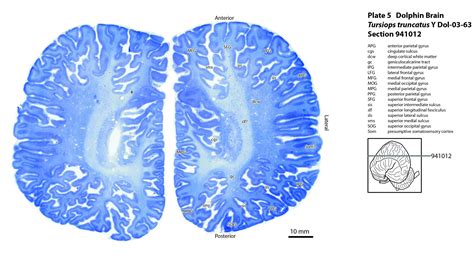

The dolphin brain is one of the most complex and highly developed among marine mammals. It is large in proportion to their body size, which is a key indicator of their advanced cognitive abilities. The brain of a dolphin is divided into several distinct regions, each responsible for different functions. These regions include the cerebral cortex, cerebellum, and limbic system.

The cerebral cortex is the outer layer of the brain and is responsible for higher-order functions such as learning, memory, and problem-solving. In dolphins, this region is highly convoluted, with numerous folds and grooves that increase the surface area and, consequently, the number of neurons. This complexity is crucial for their advanced cognitive abilities.

The cerebellum, located at the back of the brain, is responsible for coordination, balance, and motor control. In dolphins, the cerebellum is particularly well-developed, reflecting their need for precise movements and agility in the water. This region plays a vital role in their swimming, diving, and hunting behaviors.